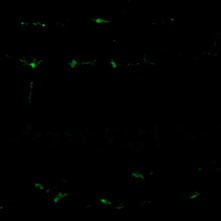

Comparison with our conventional product (rabbit polyclonal antibody)

Polyclonal Antibody

(Product No. 019-19741)

Monoclonal Antibody

(Product No. 018-28523)

Species: Rat

Site: Cerebral cortex

Sample: Frozen section

Antibody concentration: 1:200

Data by courtesy of

Dr. Nakajima, Faculty of Science and Engineering, Soka University